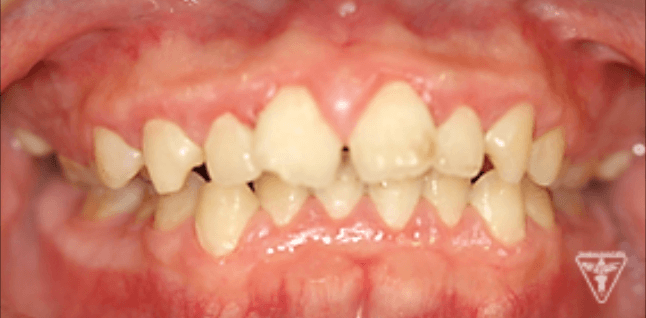

治療前